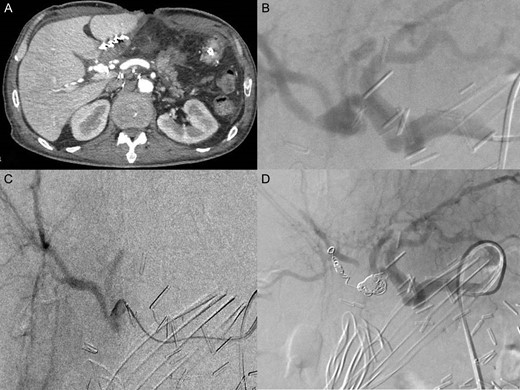

Herein, we report a case of Whipple’s procedure with child’s reconstruction performed in a 52-year-old male patient complicated with extraluminal massive hemorrhage associated with two cardiac arrests. The cause of the hemorrhage was a ruptured pseudoaneurysm of the hepatic artery. A sequential treatment with peritoneal patch as a temporary sealing and a subsequent radiological embolization was indicated (Fig. 1).

Intra-operative data (head up): (A) pringle maneuver and visualization of the hepatic artery wall tear. It is not possible to dissect or completely visualize the arteria wall. (B) declamping of the hepatic pedicle and visualization of reconstruction with peritoneum patch to sealing the artery tear.

First finding was a two liters hemoperitoneum. A huge hematoma with active bleeding was found posterior to the bilioenteric anastomosis. This latter was taken off. After evacuating the hematoma, we found an active bleeding from the hepatic pedicle that we were able to control after Pringle’s maneuver (Fig. 1). At this level, ligation of the hepatic artery could eventually stop the bleeding but with a high subsequent risk of liver ischemia. Instead, a peritoneal patch was taken from the right hypochondrium and used to cover the arterial defect creating a temporary seal effect. A new hepaticojejunal anastomosis was refashioned using the technique of Kasai. This anastomosis was intubated by a T-tube. The abdominal wall was then closed with a Negative pressure wound therapy system.